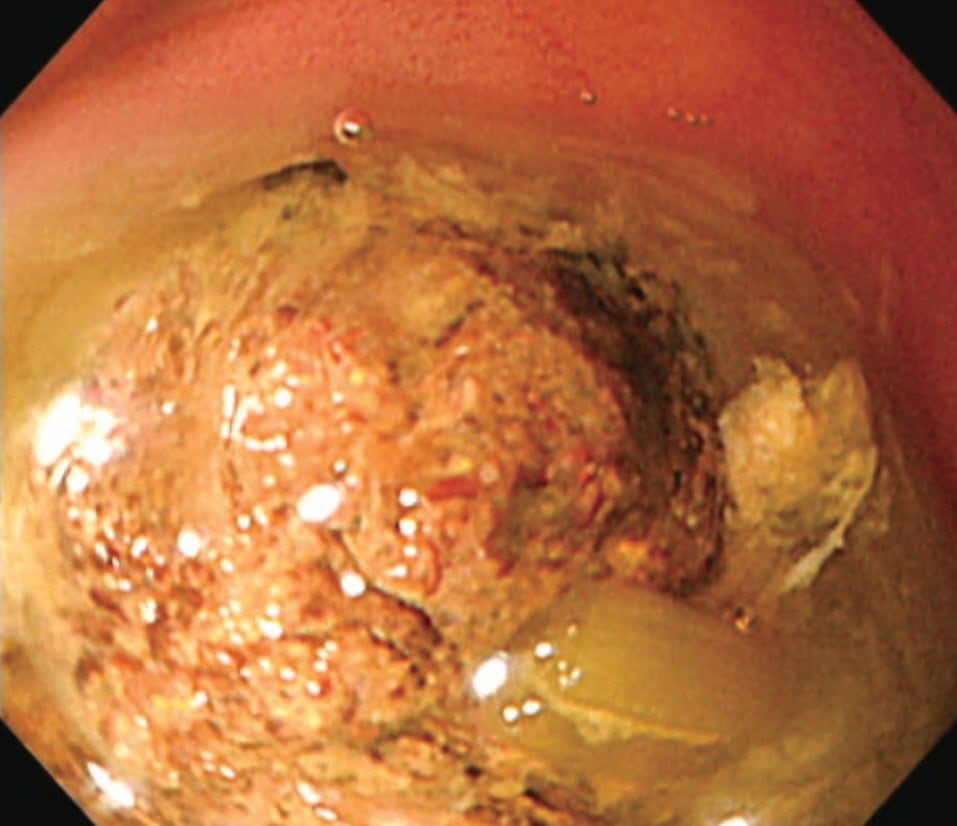

・胃内視鏡検査:不整な表面の暗褐色〜黒色塊。必要に応じて生検/回収。